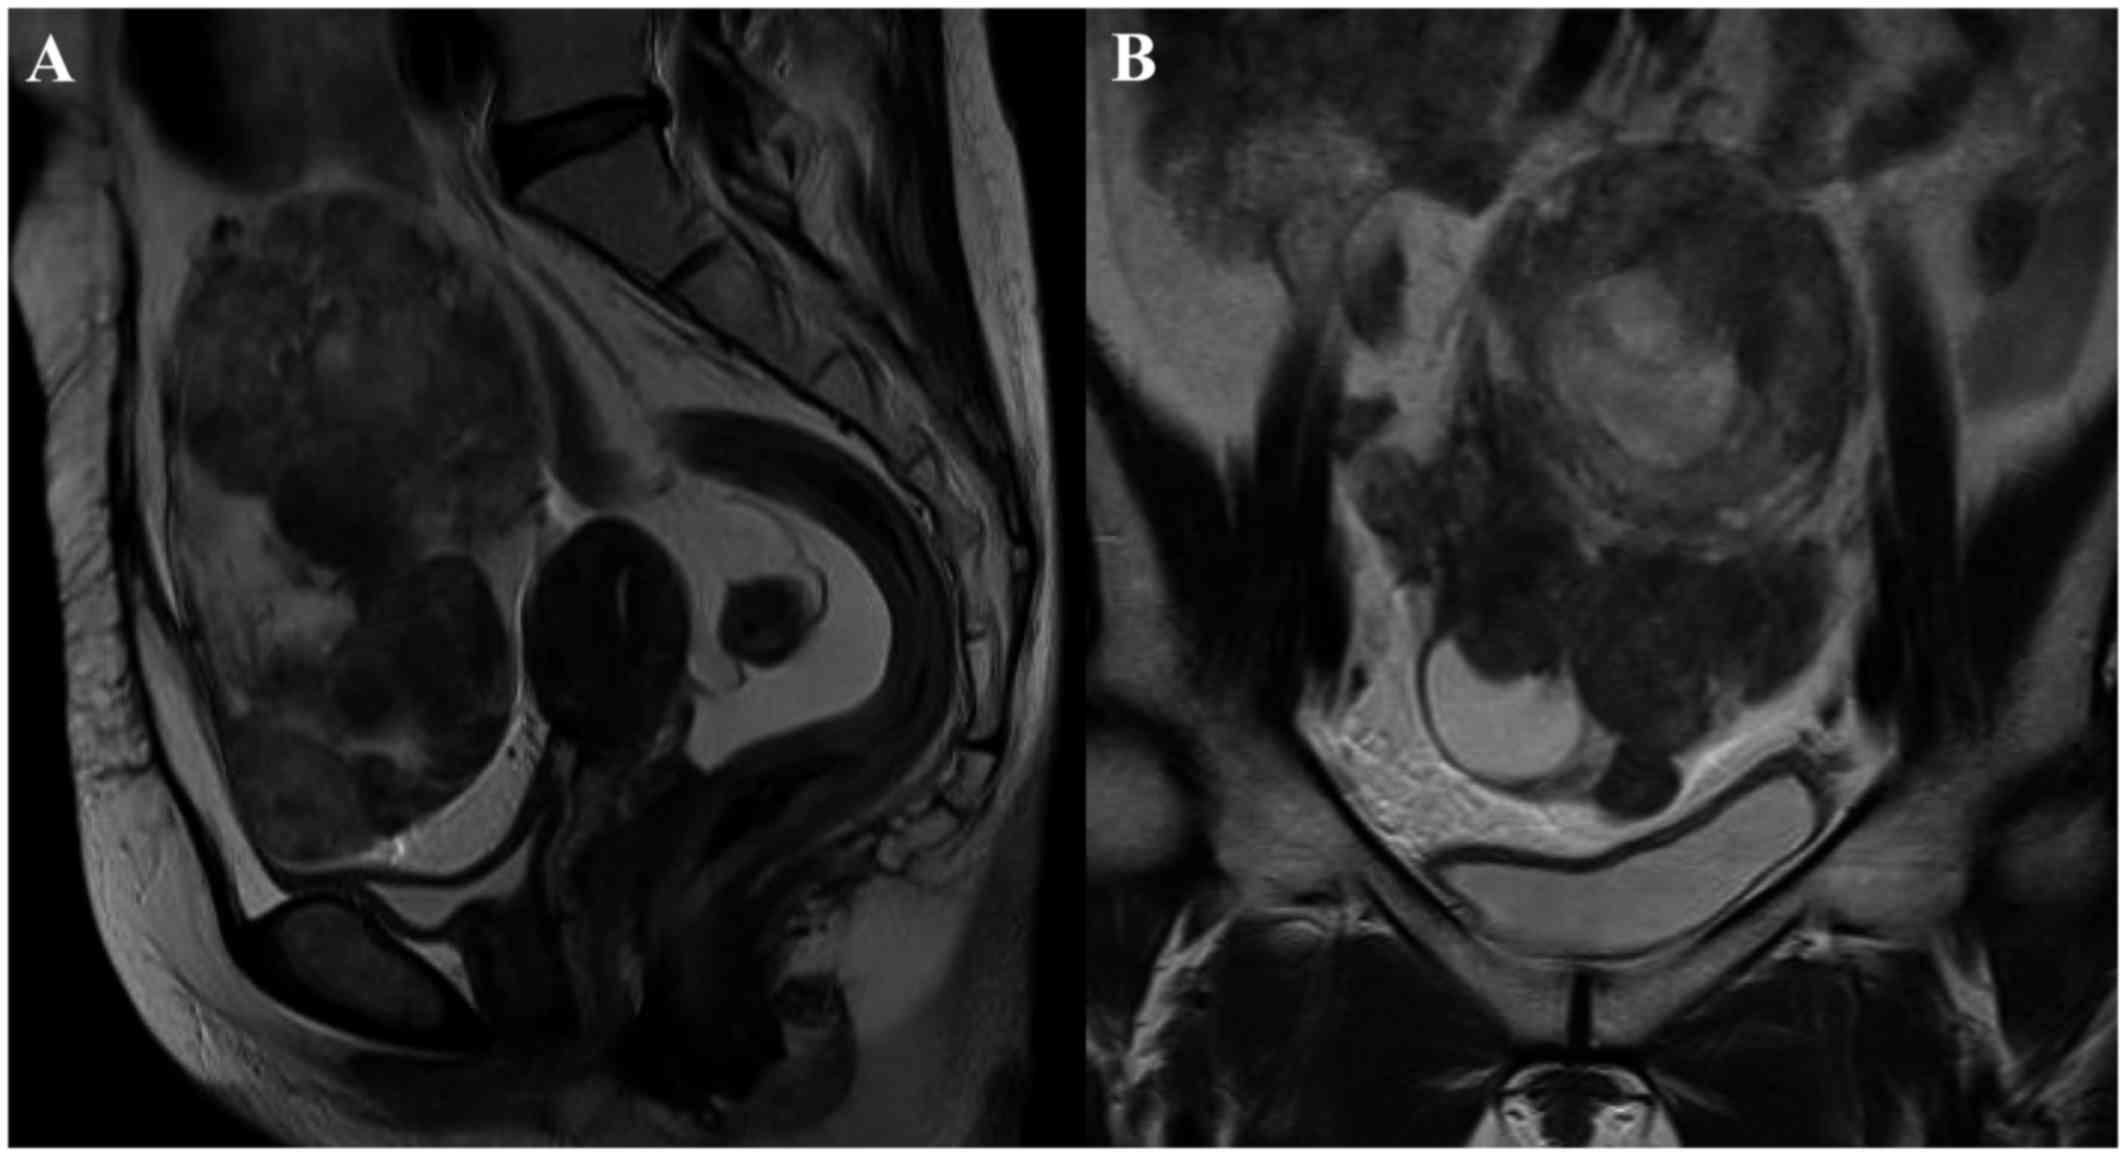

A 51-year-old multigravida woman who experienced abdominal distension for 4 months was referred to the Department of Obstetrics and Gynecology of the Hashimoto Municipal Hospital (Hashimoto, Japan) in April 2014. The patient had no history of lower abdominal or pelvic discomfort, pelvic surgery, or other relevant medical conditions. Transvaginal and transabdominal ultrasound examinations revealed a large solid abdominal mass, which exhibited iso-echogenicity. Magnetic resonance imaging (MRI) revealed a large heterogeneous mass with an irregular component occupying the lower abdominal cavity, with an intact uterus. Based on these radiological findings, the mass was suspected to be an ovarian malignancy (Fig. 1). The results of a laboratory analysis of the patient's peripheral blood revealed normal tumor marker levels [cancer antigen (CA)125, CA19-9 and carcinoembryonic antigen] and an elevated lactate dehydrogenase level (291 IU/l). Total abdominal hysterectomy and bilateral salpingo-oophorectomy were planned. Intraoperative examination revealed a solid mass arising from the lower omentum. The resected mass was 12.5×10.0×7.2 cm in size and weighed 502 g. The consistency of the mass was elastic-hard and partially soft, and its cut surface was whitish-yellow and contained a cystic and necrotic component measuring 2 cm in diameter. Microscopically, the tumor included a well-circumscribed region composed of hyaline-fibrous and mucinous-myxomatous components. The hyaline-fibrous region exhibited diffuse proliferation of spindle-shaped and small round tumor cells, with capillaries arranged in a spider's web-like pattern (Fig. 2). The mucinous-myxomatous region was composed of highly cellular tissue, which displayed a high nuclear:cytoplasmic ratio and mitotic figures. Immunohistochemistry revealed positive staining of the tumor cells for B-cell lymphoma (Bcl)-2, and partially positive staining for CD99 and epithelial membrane antigen (EMA). The tumor cells were negative for S100, α-smooth muscle actin (SMA), desmin, CD34, CD31, cytokeratin (CK)7 and CK AE1/3. The Ki-67 labeling index was 40–60%. Immunohistochemistry helped to exclude leiomyosarcoma, malignant schwannoma, gastrointestinal stromal tumor and solitary fibrous tumor. Although a qualitative analysis of mRNA expression based on a reverse transcription polymerase chain reaction (RT-PCR) assay was performed using an RNA sample extracted from formalin-fixed paraffin-embedded tumor tissue, the SYT-SSX fusion gene transcript was not detected. The diagnosis of primary omental poorly differentiated synovial sarcoma was confirmed based on the pathological findings. The patient's postoperative course was uneventful, and she was discharged from the hospital on postoperative day 7. The patient was treated with a combination of doxorubicin and ifosfamide as adjuvant chemotherapy. Despite normal findings on physical examination, 7 months after the operation a metastatic tumor was detected in the liver by positron emission tomography-computed tomography (PET-CT), and laparoscopic partial liver resection was performed, followed by adjuvant pazopanib. Twelve months after the operation, another metastatic tumor was detected in the liver by PET-CT, and the patient was again treated with laparoscopic partial liver resection followed by adjuvant pazopanib. At 14 months after the first operation, PET-CT revealed multiple recurrent metastatic tumors in the liver, lungs and pleura. Although the patient was treated with partial lung resection, aggressive metastatic tumors were detected in the liver, lungs and abdominal cavity at 2 months after the first operation. Due to the difficulty of surgical resection, the patient was treated with trabectedin, and she remained alive with stable disease at 24 months after the first operation. The patient provided written informed consent regarding the publication of the case details and associated images.

Figure 1.

Magnetic resonance imaging of omental synovial sarcoma revealing a large heterogeneous mass with an irregular component. (A) T2-weighted sagittal image (B) T2-weighted coronal image.

The diagnosis of primary omental synovial sarcoma is difficult in female patients, as surgery is required for a definitive diagnosis. In a previous study, the results of imaging analysis were non-specific (8): On MRI, T1-weighted imaging (WI) revealed areas of isointensity or hyperintensity relative to muscle in the tumor masses, and T2WI frequently showed heterogeneous signal intensity, including areas of triple signal intensity involving regions of high signal intensity that appeared fluid, isointense, or hyperintense relative to fat, and hypointense relative to fibrous tissue. In a case involving a postmenopausal female, a malignant tumor (ovarian cancer) was initially suspected due to the detection of a large abdominal mass and signs of necrosis.